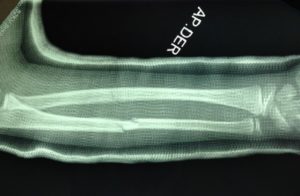

El tratamiento de las fracturas pediátricas ha evolucionado en las últimas décadas, y muchas lesiones que antes se manejaban de manera no quirúrgica ahora se están tratando quirúrgicamente. La Academia Estadounidense de Cirujanos Ortopédicos ha desarrollado pautas clínicas para ayudar a guiar la toma de decisiones y agilizar la atención al paciente para ciertas lesiones, pero muchos temas siguen siendo controvertidos *2, es importante que acudas con un experto, te dará la mejor opinión sobre los problemas del sistema músculo-esquelético de tu pequeño!!!